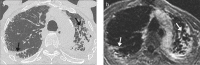

Methods: Twenty patients with idiopathic pulmonary fibrosis (IPF) and twelve control patients underwent late-enhanced MRI and high-resolution CT. Tissue characterization of PF was depicted using a segmented inversion-recovery turbo low-angle shot MRI sequence. Pulmonary arterial blood pool nulling was achieved by nulling main pulmonary artery signal. Images were read in random order by a blinded reader for presence and extent of overall PF (reticulation and honeycombing) at five anatomic levels. Overall extent of IPF was estimated to the nearest 5% as well as an evaluation of the ratios of IPF made up of reticulation and honeycombing. Overall grade of severity was dependent on the extent of reticulation and honeycombing.

Results: No control patient exhibited contrast enhancement on lung late-enhanced MRI. All IPF patients were identified with late-enhanced MRI. Mean signal intensity of the late-enhanced fibrotic lung was 31.8±10.6 vs. 10.5±1.6 for normal lung regions, P < 0.001, resulting in a percent elevation in signal intensity from PF of 204.8%±90.6 compared with the signal intensity of normal lung. The mean contrast-to-noise ratio was 22.8±10.7. Late-enhanced MRI correlated significantly with chest CT for the extent of PF (R=0.78, P = 0.001) but not for reticulation, honeycombing, or coarseness of reticulation or honeycombing.

Conclusion: Tissue characterization of IPF is possible using inversion recovery sequence thoracic MRI.